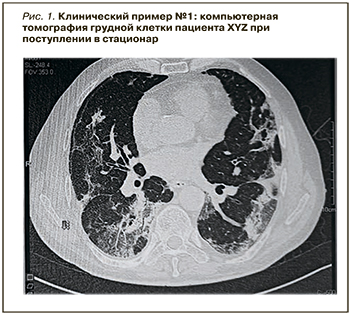

На картине КТ грудной клетки – классические признаки коронавирусной инфекции (рис. 1).

Был сформулирован следующий диагноз:

- U07.1. Новая коронавирусная инфекция COVID-19, вирус идентифицирован, тяжелая форма;

- J12.8. Внебольничная вирусно-бактериальная пневмония, двусторонняя, полисегментарная, тяжелой степени тяжести, КТ-4, дыхательная недостаточность степени 2 (ДН2);

- гипертоническая болезнь стадии 2, артериальная гипертензия степени 1, группа риска 3 (курение, дислипидемия, гиперхолестеринемия).